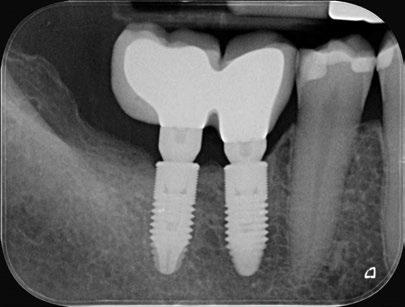

Seguidamente, se colocaron los pilares cónicos TSV-TM de Zimmer® y se atornillaron los pilares provisionales de titanio (Figuras 17-23).

A las 24 horas se citó al paciente nuevamente, se atornilló el provisional en boca y se realizó una

Figura 27. Ortopantomografía del provisional atornillado en boca para verificar ajuste.

ortopantomografía de verificación del ajuste pasivo de todos los implantes. Por último, tapamos las chimeneas con teflón y resina provisional y se chequeó nuevamente la oclusión, dando nuevamente las instrucciones de higiene y mantenimiento de la prótesis provisional (Figuras 24-27).